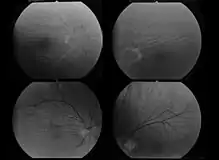

Choroid folds in high hyperopia (fluorescein angiography)